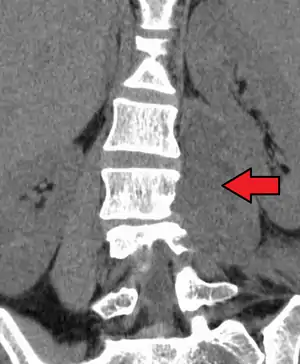

An abscess in the psoas muscle of the abdomen may be caused by lumbar tuberculosis. Owing to the proximal attachments of the iliopsoas, such an abscess may drain inferiorly into the upper medial thigh and present as a swelling in the region. The sheath of the muscle arises from the lumbar vertebrae and the intervertebral discs between the vertebrae. The disc is more susceptible to infection, from tuberculosis and Salmonella discitis. The infection can spread into the psoas muscle sheath.[1]

Paraspinal abscess in the psoas muscle